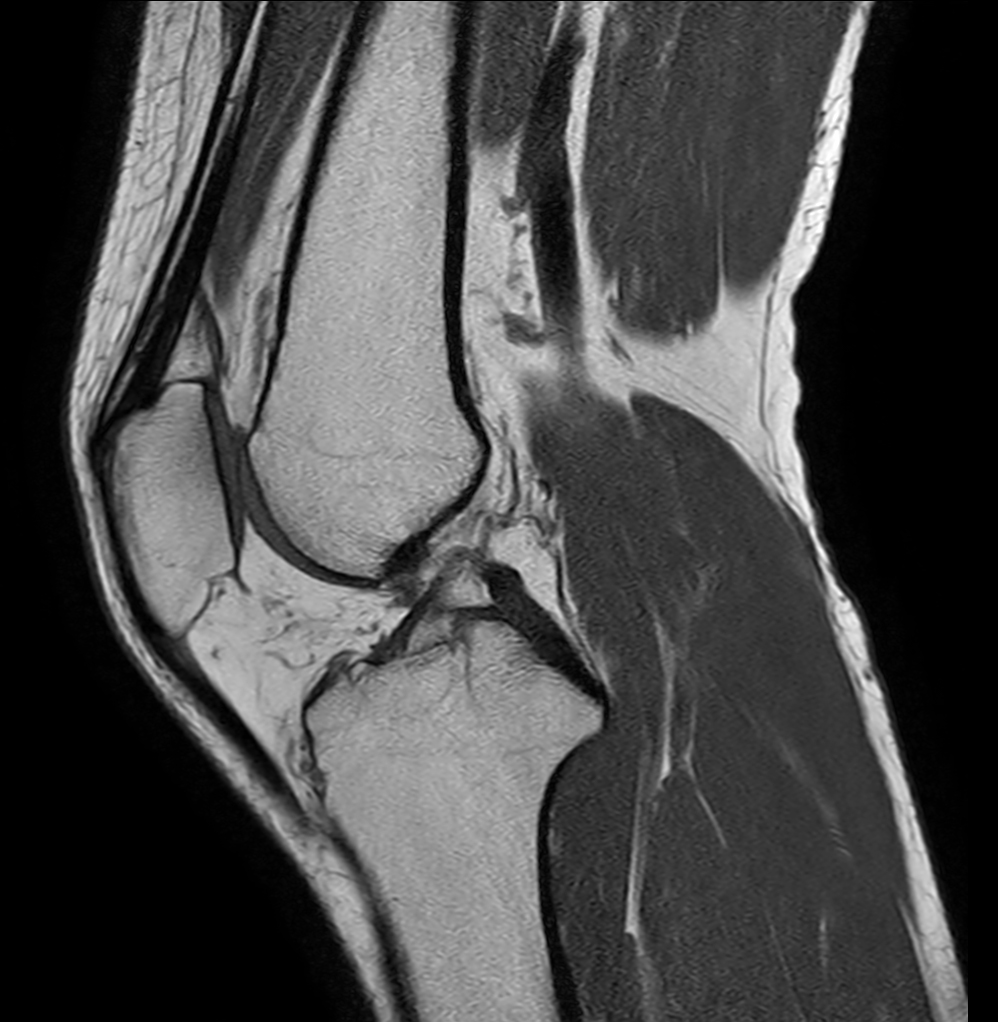

Sagittal PDw TSE